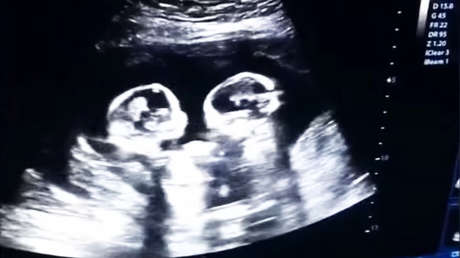

El video de una ecografía realizada en Yinchuan (Ningxia, China) en la que se ve a dos hermanas gemelas 'peleándose' dentro del vientre de su madre, se ha vuelto viral desde que este lunes apareciera en las redes sociales.

En la grabación, realizada por el padre el pasado mes de diciembre, se observa la pugna de los fetos, de tan solo cuatro meses, que parecen sacudirse patadas y puñetazos.

Se trata de un extraño tipo de embarazo de riesgo en el que las gemelas comparten saco amniótico y placenta dentro del útero. Las dos nacieron sanas el pasado 8 de abril mediante cesárea.